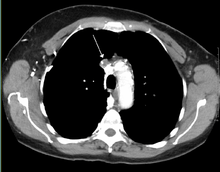

The main techniques of diagnosing SVCS are with chest X-rays (CXR), CT scans, transbronchial needle aspiration at bronchoscopy and mediastinoscopy.[3] CXRs provide the ability to show mediastinal widening and may show the presenting primary cause of SVCS.[3] CT scans should be contrast enhanced and be taken on the neck, chest, lower abdomen and pelvis.[3] They may also show the underlying cause and the extent to which the disease has progressed.[3]